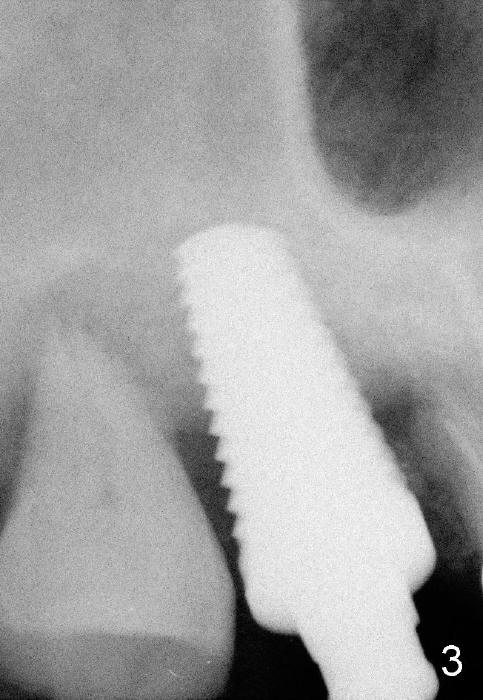

The 60-year-old man is a bruxer. All of the three upper right molars are nonsalvageable (Fig.1). Since #2 is symptomatic, it is planned to be extracted and restored first. As expected, there is severe alveolar destruction (single large socket), while the base bone is solid. A series of tapered osteotomes (2-5 mm) are used to create osteotomy in the base bone (gaining 4 mm into new bone), followed by 4.5x20 mm tap at the depth of 17 mm from the gingival margin (Fig.2). Then the depth is adjusted to 14 mm; the bone expansion and osteotomy continue until using 7 mm tap with good binding to the bone (Fig.3). A 7x14 mm implant is placed with insertion torque more than 60 Ncm (Fig.4). No bone graft is used for sinus lift considering sinus membrane perforation. The buccal flap is raised to reveal bony defect, which is covered by Osteogen (a synthetic bone graft) and then collagen membrane (Fig.6 *). Five days postop, the membrane undergoes a type of transformation (Fig.7 *) leading to a gingival tissue (Fig.8 *, 18 days postop). By 3 months, the gingiva has normal appearance (Fig.9), while the implant seems to be osteointegrated (Fig.10). Once the infected source is removed, our body has potential to regenerate.